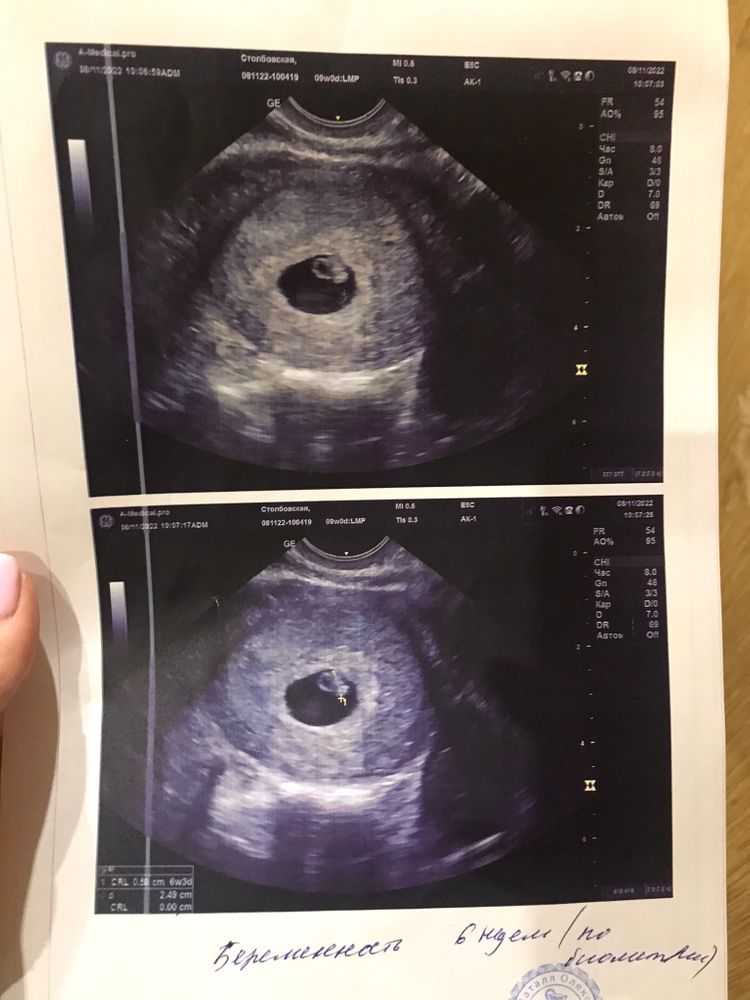

Вообщем вчера ходила на узи. Показали мне мое кольцо с бриллиантом 💍,нам 6 недель и 3 дня. Я так рада и счастлива. 4 года пытались и чудо, всем желаю такого счастья ❤️💋🐥 у нас уже бьется сердечко 💓